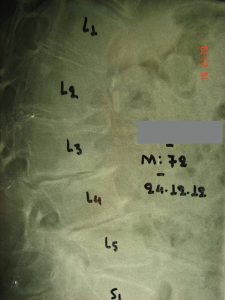

Εικόνα 8 (α,β,γ,δ,) : Πλαγία προεγχειρητική ακτινογραφία (α) της Θωρακο-Οσφυϊκής Μοίρας της Σπονδυλικής Στήλης (Θ-Ο.ΜΣΣ). Παρατηρείται μεγάλη θωρακο-οσφυϊκή κύφωση που προκαλεί διαταραχή της ισορροπίας του κορμού. Προεγχειρητικός σχεδιασμός (β) για την αποκατάσταση οσφυϊκής λόρδωσης στο φυσιολογικό. Μετεγχειρητική προσθιοπισθία (γ) και πλαγία (δ) ακτινογραφία. Παρατηρείται αποκατάσταση της οσφυϊκής λόρδωσης στο φυσιολογικό.